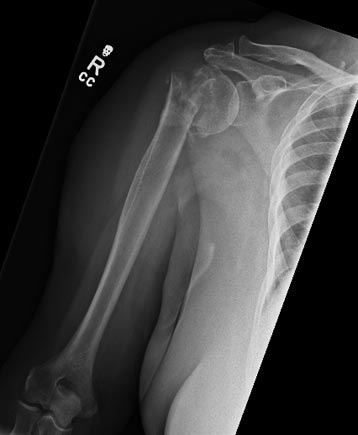

Non-united Fracture of Proximal Humerus